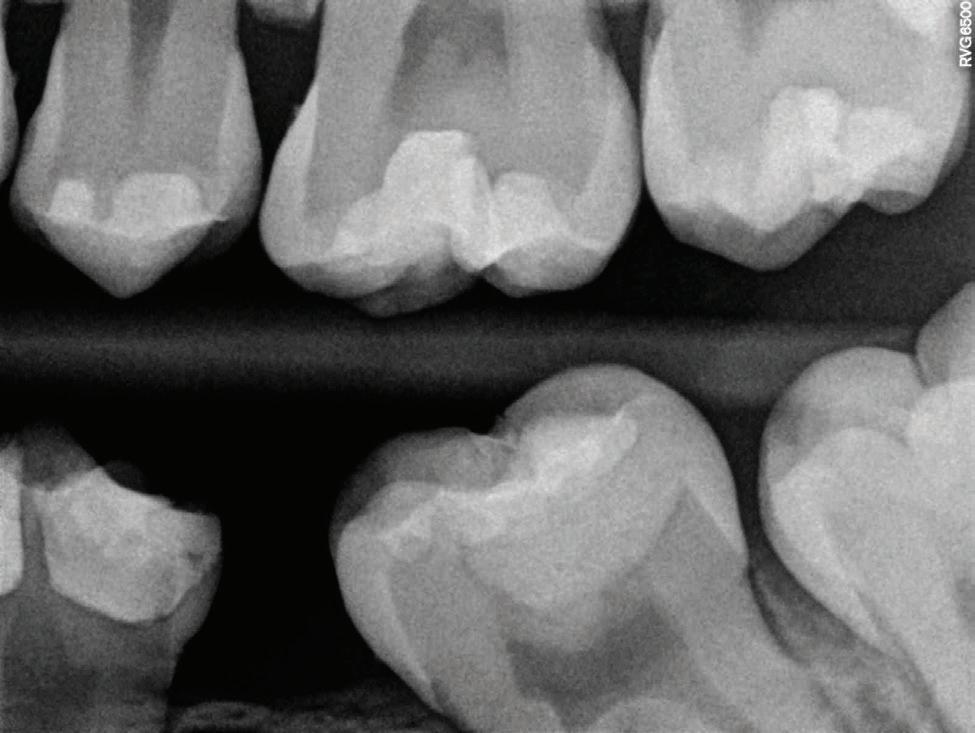

Clear radiographs are essential to accurate diagnosis and are a special test that dentists per form regularly many times throughout the day. Following the ALARA principle, we want to ensure we take a minimal number of radio graphs to ensure low radiation dosage so to repeat radiographs due to operator error should be avoided. The use of film holders allow the clinician to visualise how the radiographs should be taken to optimise the clarity of the image and ensure the diagnostic value of the image. Hawe Solutions x-ray film holders...

Figure 1: Radiographic Image of implants do not demonstrate bone loss due to the bisecting angle of the radiograph taken.

Figure 2: Radiographic image in a paralleling technique of implants dem onstrate moderate peri-implantitis with bone loss that will necessitate treatment.

• Allow exact posi tioning of the film or phosphor plate relative to the tooth - no bending and thus no distortion;

• Require no guesswork - exclusive, automatic reliance on the extraoral aiming and centring device;

• Deliver semi-reproducible images (quasi standardisation)the use of film holders allows some sense of reproducibility for assessment over time; and

• Produce optimally clear radiographs.